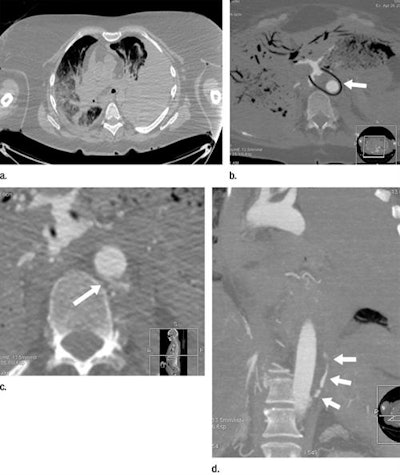

Postmortem CT (a) and postmortem CT angiography (b-d) scans of a 59-year-old woman who died of internal exsanguination soon after Whipple surgery. All images courtesy of RSNA.The group acquired CT and CT angiography scans of the bodies within five days of death. A forensic pathologist and a radiologist, both with more than five years of experience in reading postmortem CT angiography data, evaluated the scans individually. A second forensic pathologist conducted the autopsy for each case on the same or following day.